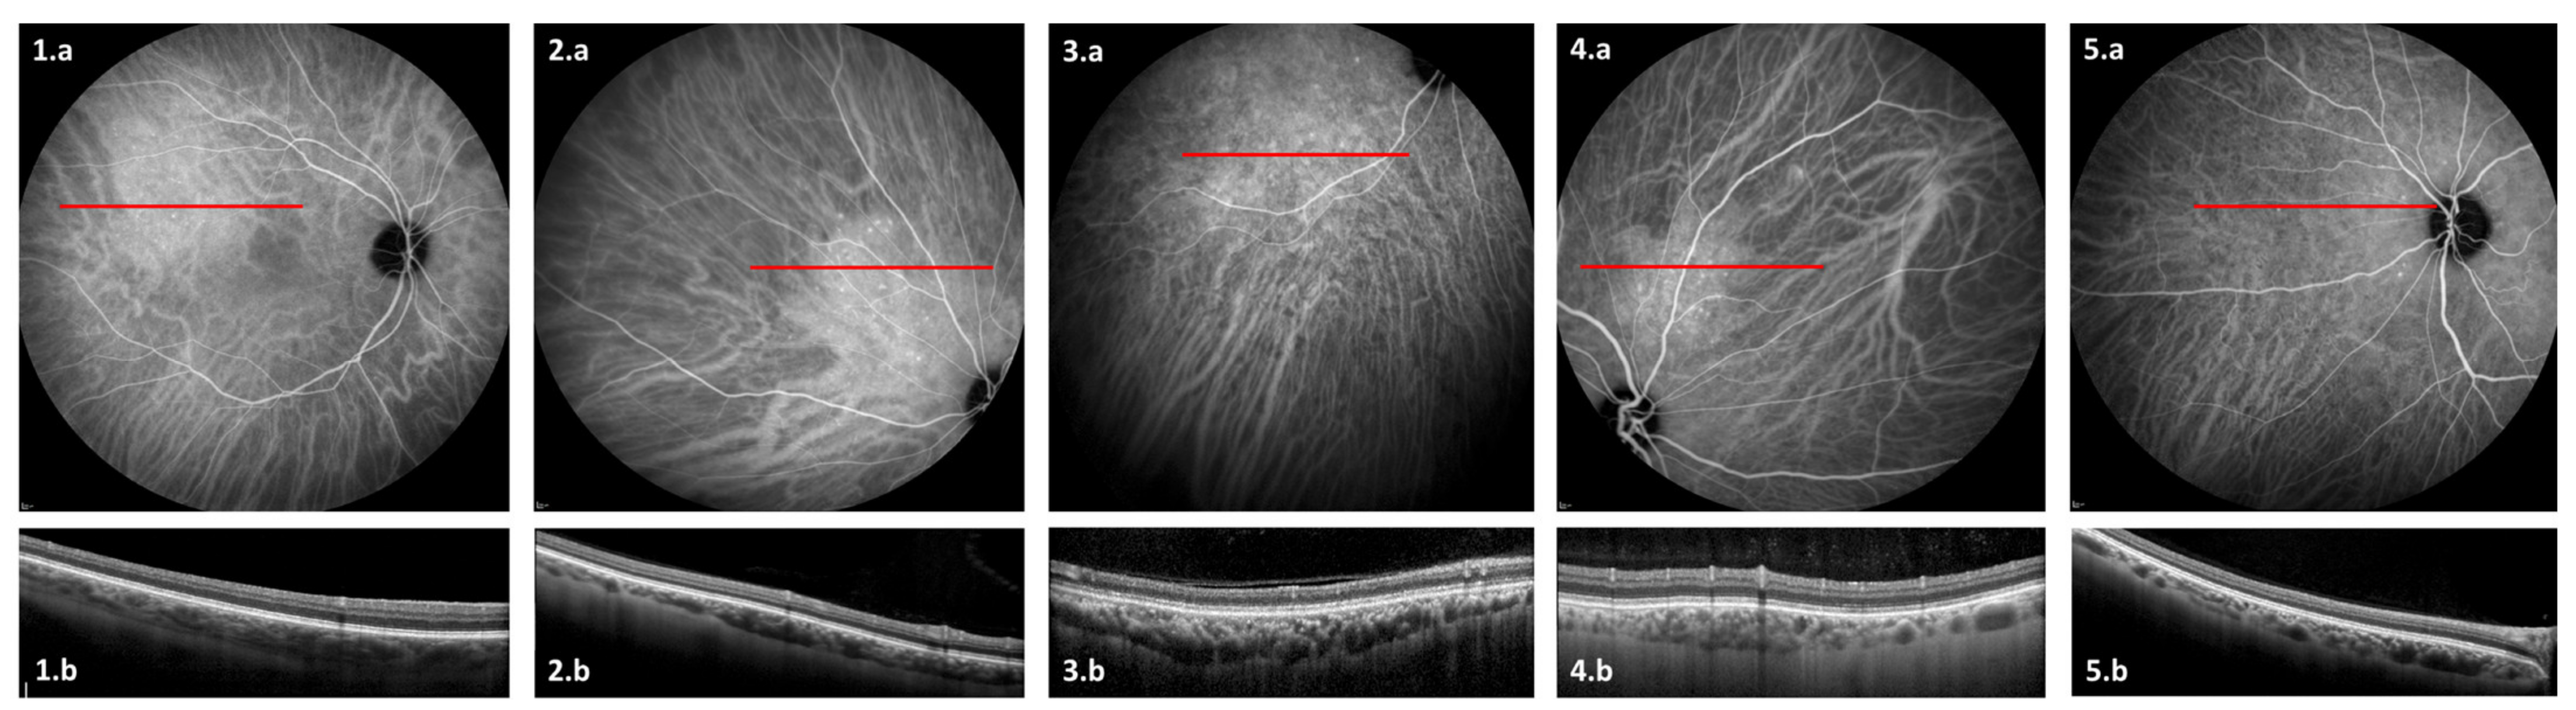

3.3. ICGA Findings

| Vessel leakage and/or staining Hypofluorescent spots Pintpoint leakage Intervortex shunts “Hemangioma-like” lesion | 20 (71%) 19 (68%) 15 (54%) 10 (36%) 5 (18%) |

| OCT anomalies | Number of eyes (%) |

| Pachyvessels Focal choroidal thickening Caverns | 25 (89%) 7 (25%) 6 (21%) |

| 6 | Female | 27 | Idiopathic cerebral hypertension | NA | No | No | Yes | No | No | No | Yes | No | Yes | No | Papillary edema |

| 7 | Male | 66 | ARDS | ND | Yes | No | Yes | Yes | Yes | Yes | Yes | Yes | Yes | Yes | |

| 8 | Male | 55 | ARDS | Severe | Yes | Yes | Yes | No | Yes | Yes | Yes | No | Yes | Yes | |

| 9 | Male | 74 | Ischemic CVA | NA | No | No | Yes | No | No | No | Yes | No | Yes | No | Pseudodrusen |

| 10 | Male | 59 | Ischemic CVA | NA | No | No | Yes | Yes | Yes | Yes | Yes | Yes | Yes | No | |